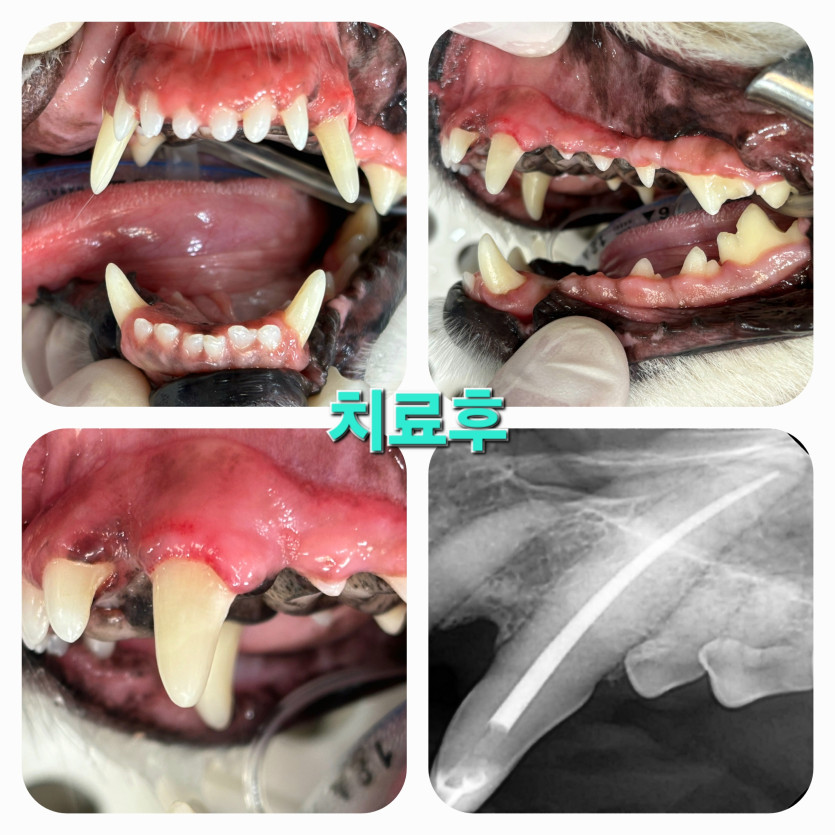

누룽지의 송곳니 파절, 신경치료, 레진수복 치료후기

수술 마치고 활발하게 움직이는 아이보니 마음이 놓이네요.

친절히 설명해주시는 의사쌤, 직원분 덕분에 안심하고 돌아갑니다.